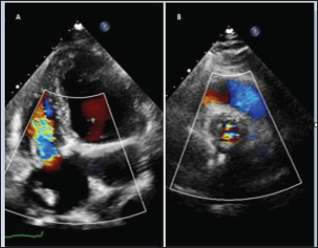

The instituted targeted antibiotic therapy let the patient progressed favorably with significantly reduction of inflammatory markers and PCT. After two negative blood coltures the patients was transferred to internal medicine ward and the antibiotic therapy was reduced after 3 weeks by means of linezolid (1200mg /24h ev) and Daptomicin (1000mg/ die ev). After 10 days, for recurrence of fever, Piperacillin/tazobactam (4.5gr every 6 hours ev) was added. After more ten days of antibiotic therapy the patients was so transferred to our hospital for surgical treatment, in stable clinical and hemodynamic conditions, but persistent fever. Coronary angiograms reveal no coronary artery disease and the preoperative echo confirmed the huge vegetations on tricuspid (Figure 1A) and aortic valves (Figure 1B) and severe eccentric aortic regurgitation jet (Figure 1C). The Chest X Ray suggested a persistent left superior vena cava (Figure 2).

Figure 1: Preoperative Echo showing the huge vegetations on tricuspid (A) and aortic (B) valves and the eccentric aortic regurgitation jet (C).